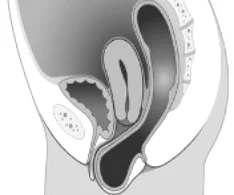

Ďalšie dysfunkcie panvového dna – cystokela, retrokela, prolaps maternice, avulzné poranenie svalov panvového dna.

Prolaps uteru

Rektokéla